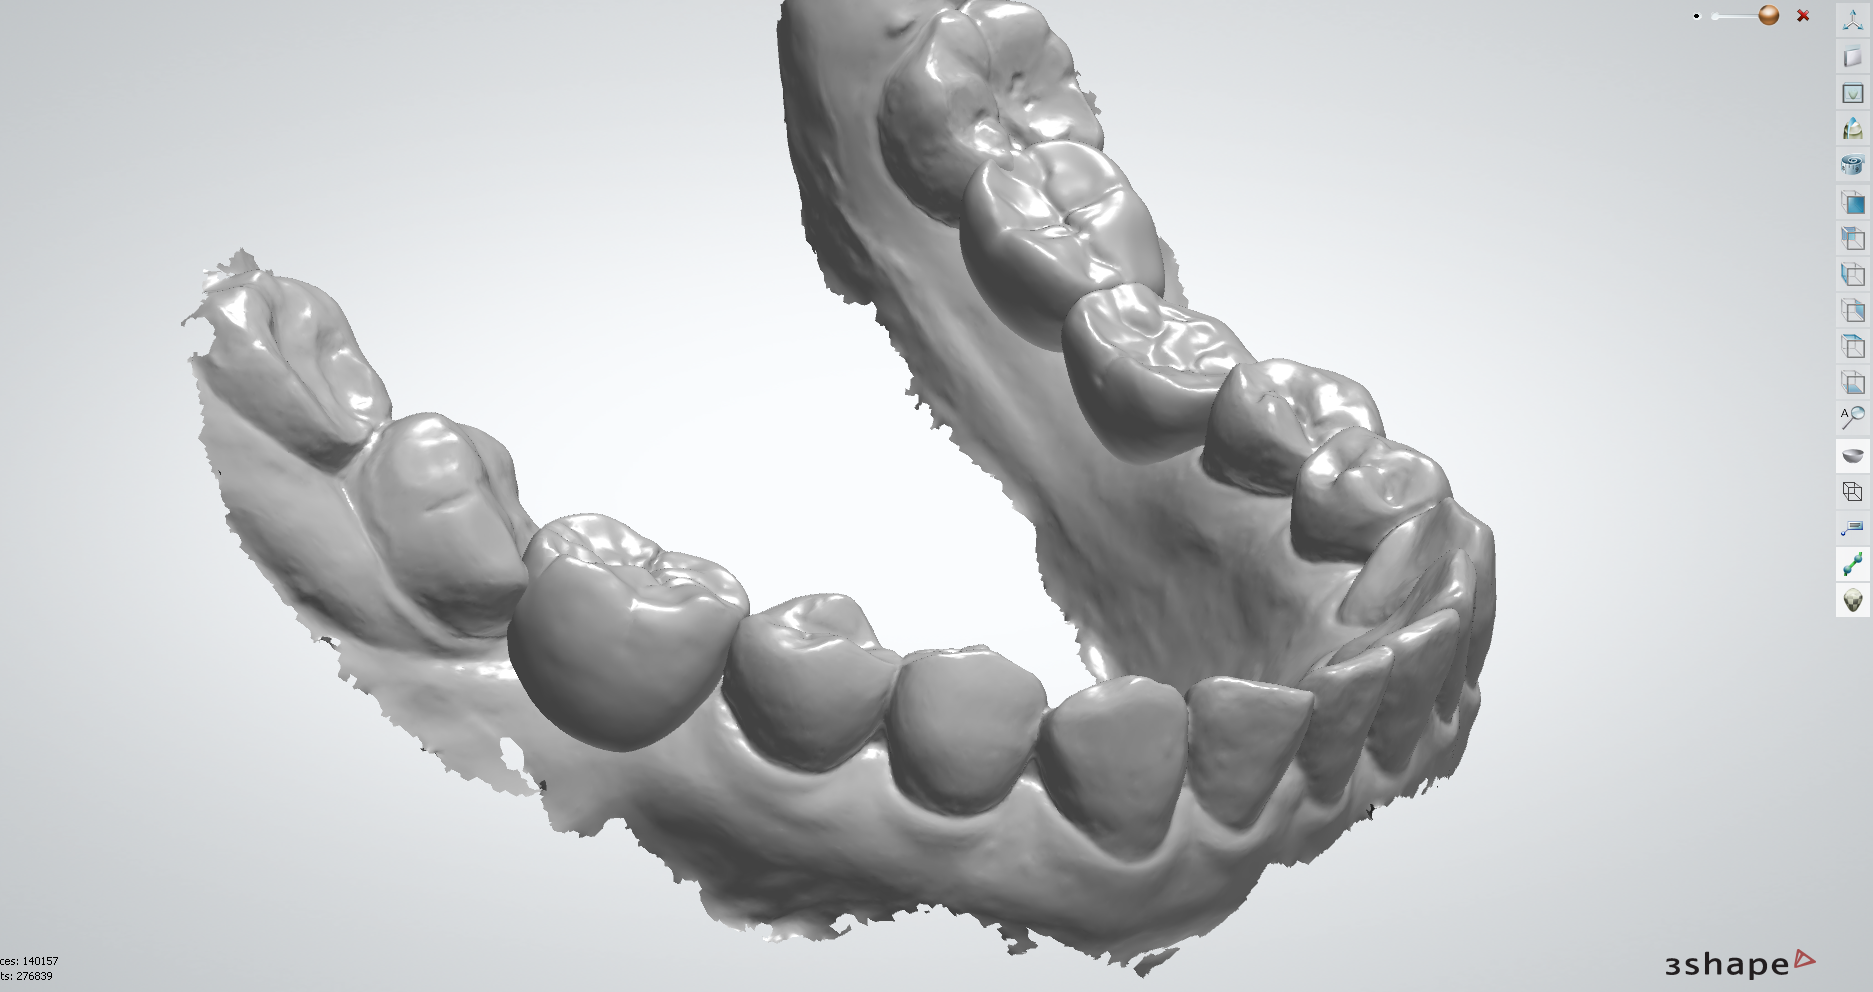

| 丹麥3shape口內掃描機 取代傳統印模方式,降低印模時的不適感,將口內缺齒情形以3D清楚呈現。 |

在術前規劃會使用數位化設計軟體,利用數位印模和數位排牙,精準地設計未來的牙齒排列和咬合狀態,更能真實模擬未來正式假牙效果,讓假牙設計既貼合個人需求,也更接近理想的美觀與舒適。

醫師置入植體後,等待骨癒合完成會讓植體露出來,進行數位印模,並交給數位牙技師製作正式假牙。

數位牙體技術師利用數位軟體在電腦影像上設計假牙外型,並以精密四軸或五軸研磨機器,完成假牙製作。